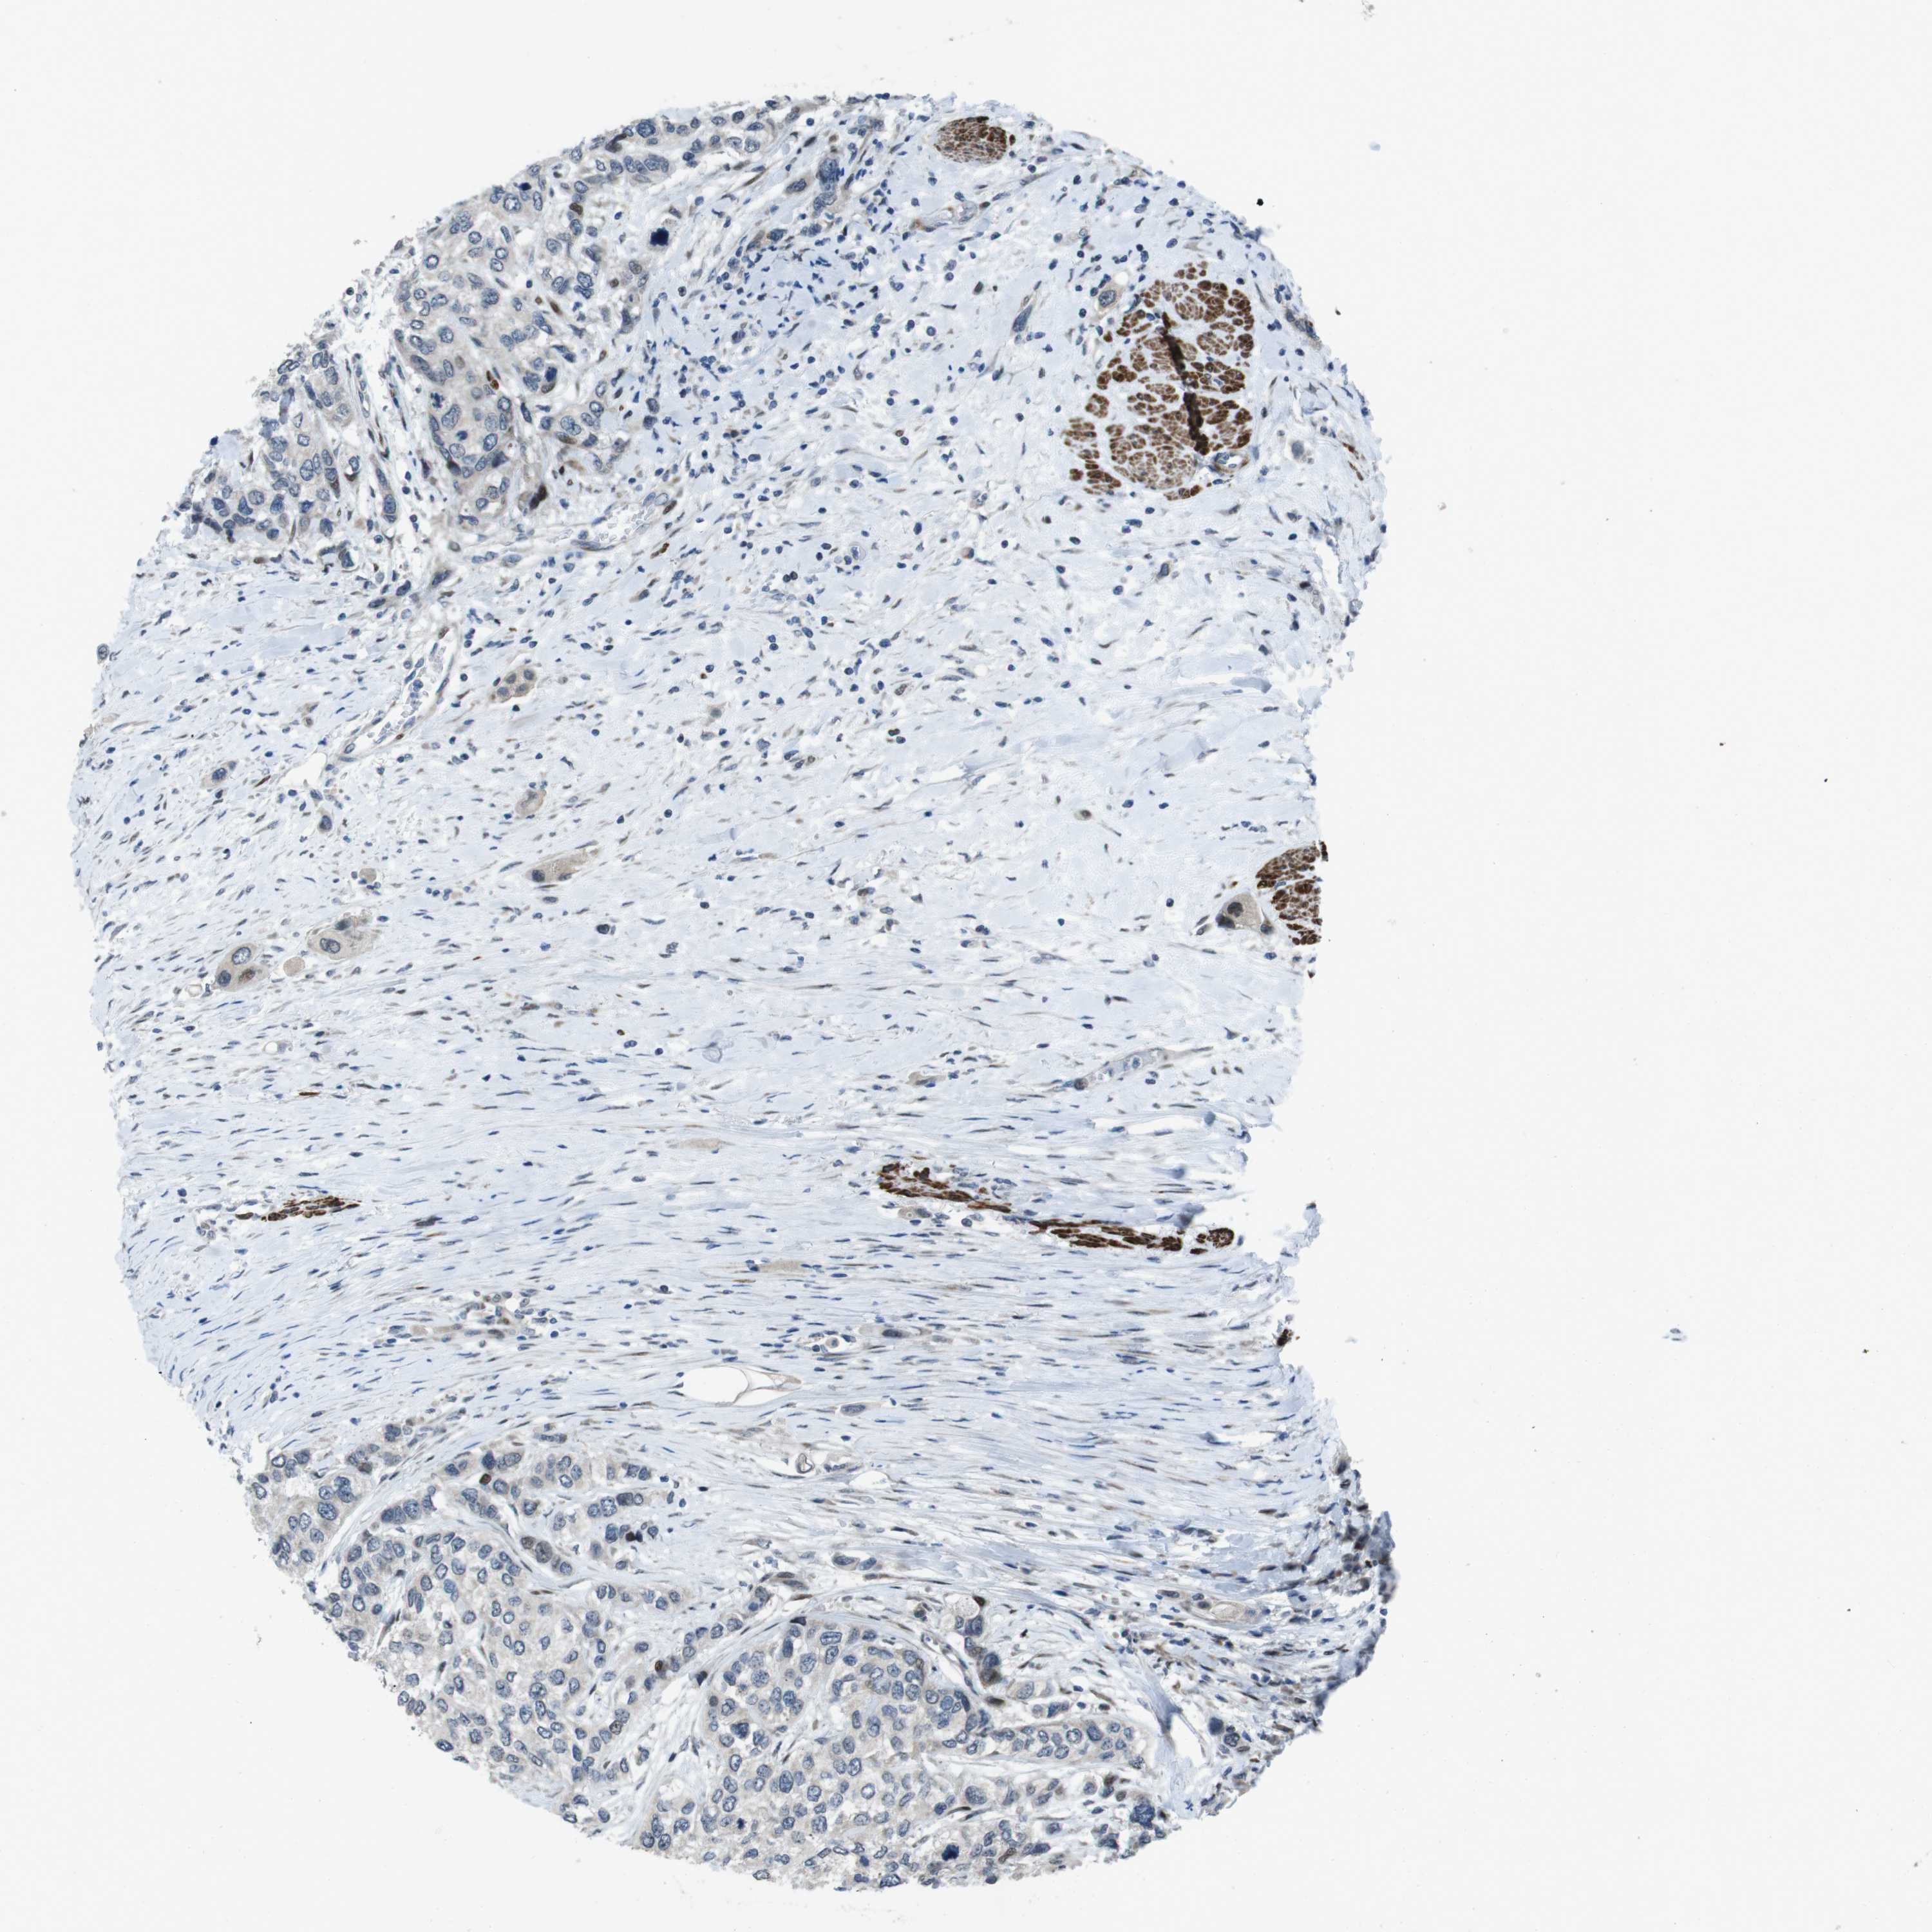

UROTHELIAL CANCER - Protein expressioni

A mouse-over function shows sample information and annotation data. Click on an image to view it in a full screen mode. Samples can be filtered based on level of antibody staining by selecting one or several of the following categories: high, medium, low and not detected. The assay and annotation is described here.

Note that samples used for immunohistochemistry by the Human Protein Atlas do not correspond to samples in the TCGA dataset.

Antibody stainingi

Antibody staining in the annotated cell types in the current human tissue is reported as not detected, low, medium, or high, based on conventional immunohistochemistry profiling in selected tissues. This score is based on the combination of the staining intensity and fraction of stained cells.

Each image is clickable and will lead to virtual microscopy that enables deeper exploration of all samples and also displays staining intensity scores, fraction scores and subcellular localization as well as patient and tissue information for each sample.

Antibody HPA015629

Staining

High

Medium

Low

Not detected

Intensity

Strong

Moderate

Weak

Negative

Quantity

>75%

75%-25%

<25%

None

Location

Nuclear

Cytoplasmic/membranous

Cytoplasmic/membranous,nuclear

Urothelial carcinoma, High grade